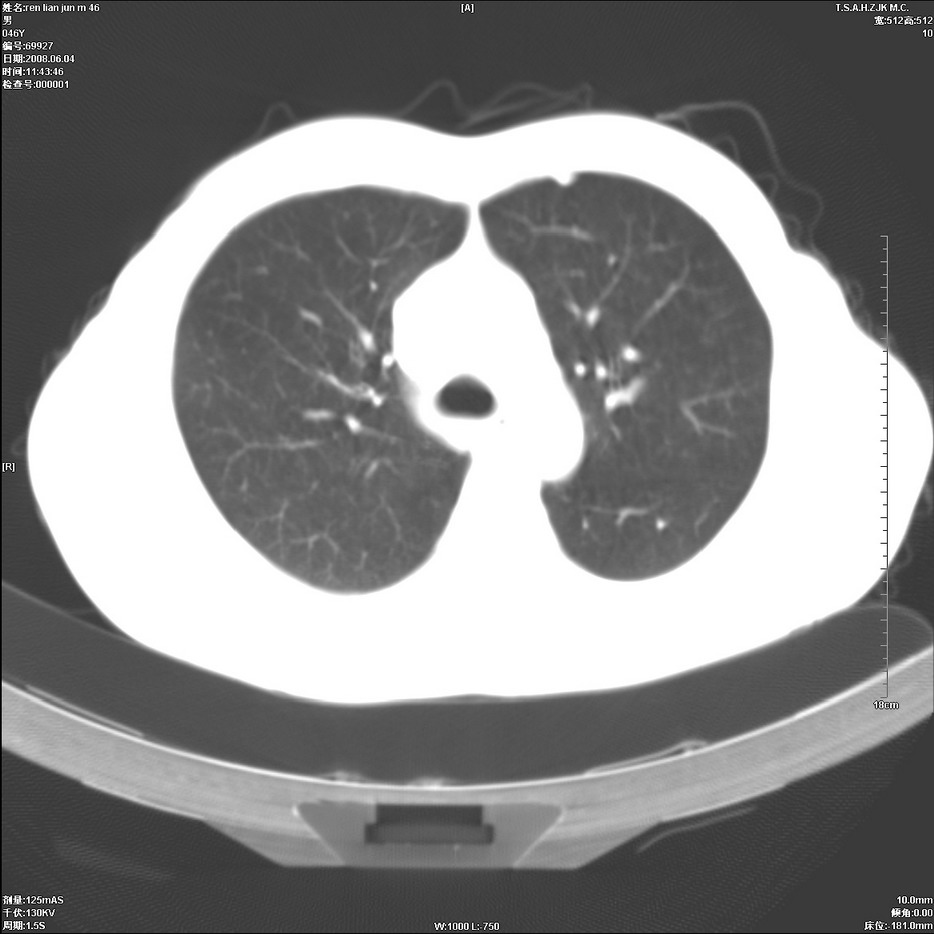

以下是引用qiu999在2008-6-5 17:14:00的发言:[br]考虑右肺中心型肺癌.颅内应做增强检查.

以下是引用形影不离在2008-6-5 19:18:00的发言:[br]右肺中心型肺癌并纵隔及左侧腋窝淋巴结转移,颅内应做增强检查。

以下是引用杀毒软件在2008-6-5 18:33:00的发言:[br]支持考虑右肺中心型肺癌,颅内病变是不是转移,不好说